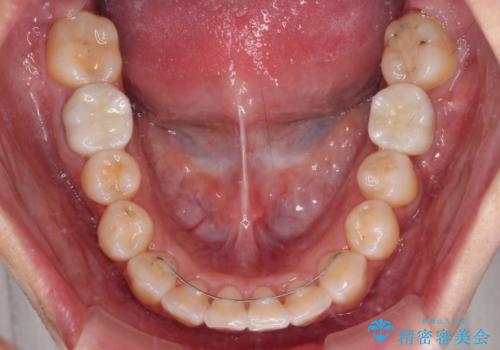

口元の突出感は少なく、下顎の叢生は軽微なものであったので、叢生の強い上顎左右の小臼歯を1本ずつ抜歯し、ワイヤー装置にて矯正治療を行うこととしました。

矯正治療を行う前に、根管治療の必要な上顎前歯と下顎大臼歯の根管治療を行い、矯正治療の途中で下顎の欠損部にインプラント埋入することとし、矯正治療後に補綴治療を行うこととしました。

矯正治療中にインプラント埋入を行うなど、余計な時間や無駄のない治療を行うことができました。